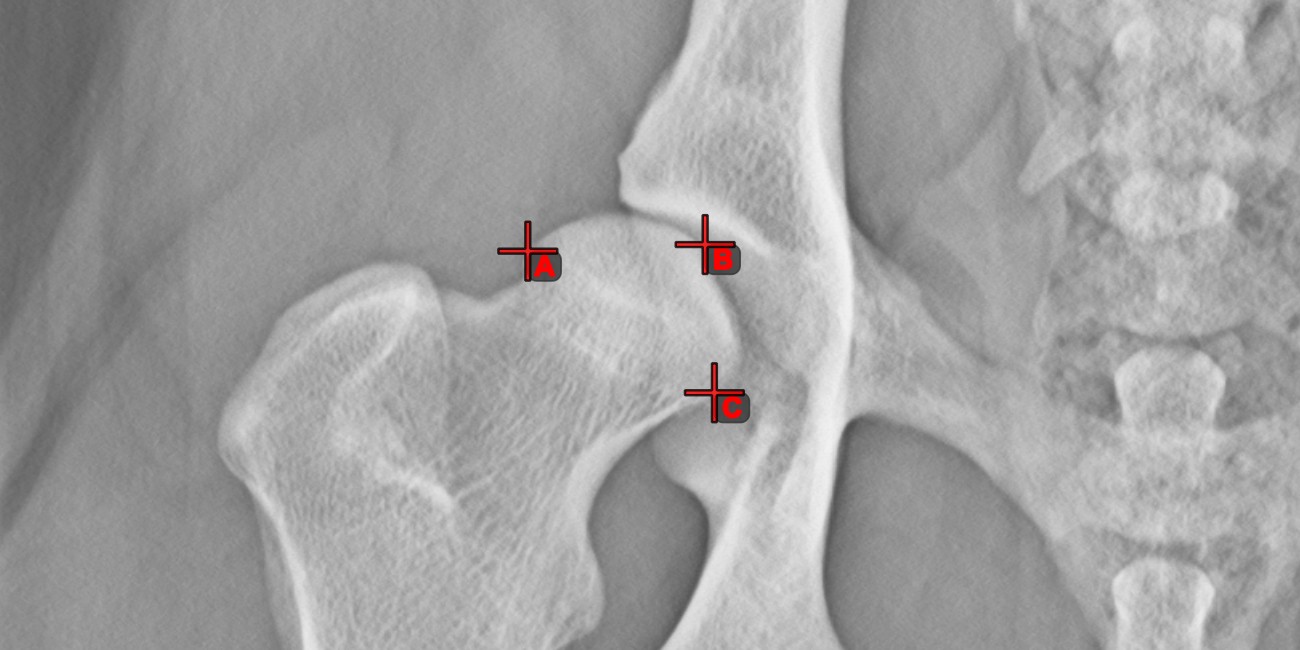

Measurement Point

Mark simple points on the image using the Measurement Point tool. Each point is assigned with a letter for better identification.

Modify the position of the points on the image by using the Select/Move Item tool. Select the point by using the assigned mouse button of the tool, and then move it freely anywhere on the image.

../_images/image235.jpg